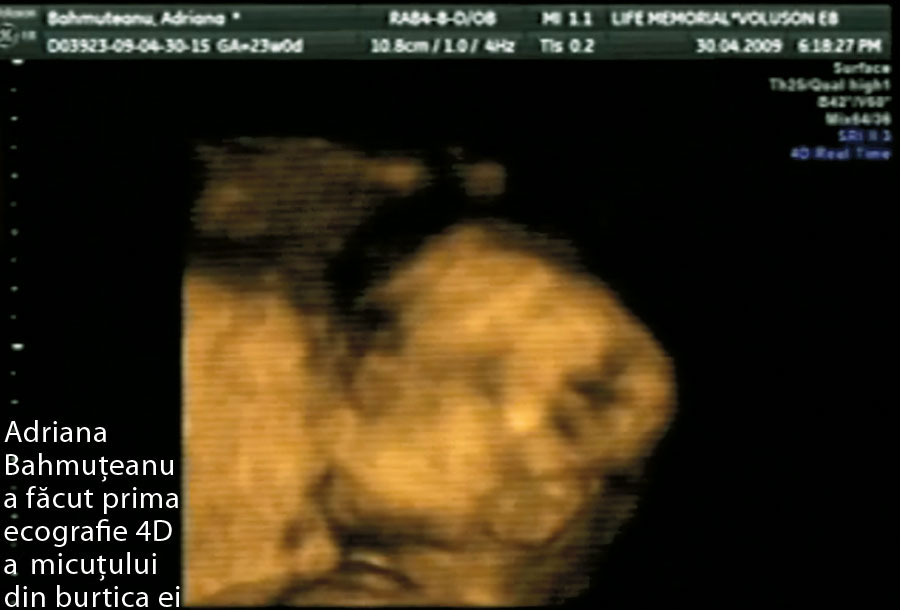

Însoţită de Silviu Prigoană, Adriana a aşteptat aproape două ore, pentru ca dr. Dimitrie Pelinescu Onciul să poată vedea faţa copilului. Lui Silviu Prigoană aproape i-au dat lacrimile de emoţie când şi-a văzut bebeluşul şi a declarat că, în mod cert, seamănă cu Maximus, primul lor băiat. “Am fost la cel mai performant ecograf din lume, care arată dacă fetusul are vreo malformaţie. După consultaţie, am aflat că micuţul se dezvoltă bine şi e perfect sănătos. A trebuit să stau două ore pentru a-i putea vedea faţa, deoarece nu a vrut să se arate şi a stat mai mult ascuns”, ne-a declarat Bahmu. Cel de-al doilea copil al lui Silviu Prigoană şi al Adrianei Bahmuţeanu se va naşte la începutul lunii august.